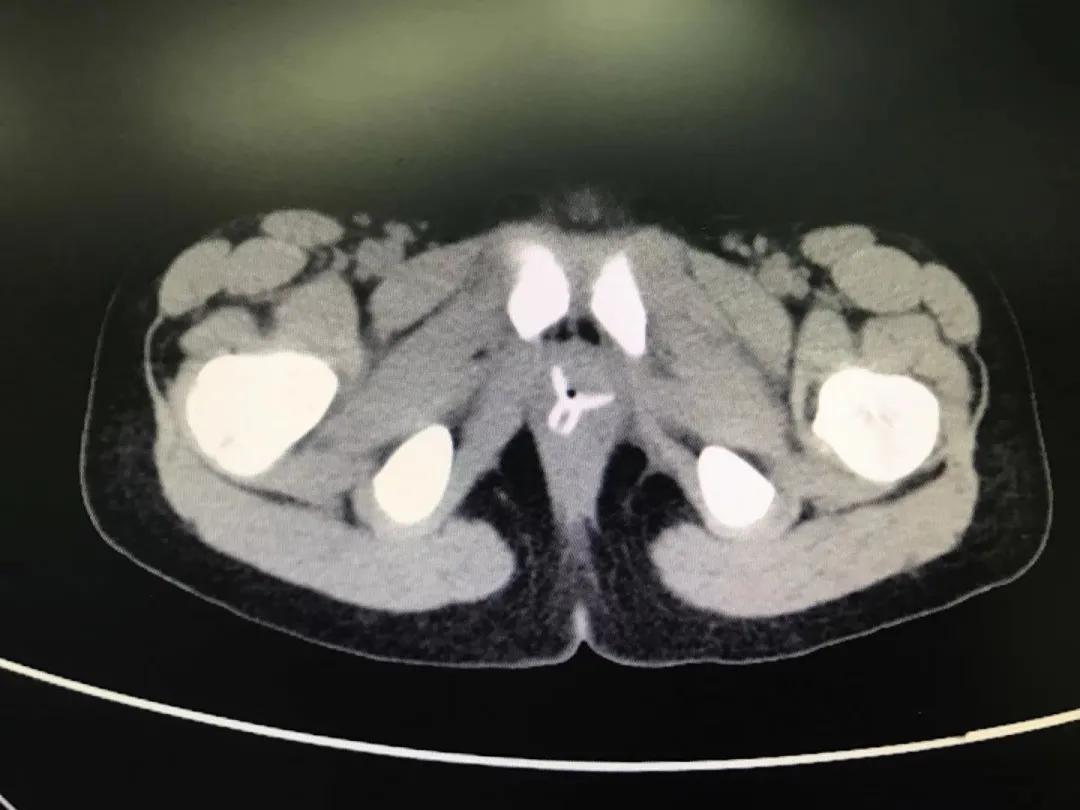

患儿晚上七点多被送至南京市儿童医院,泌尿外科汪俊主治医师立即安排了急诊手术。“幸好玻璃珠并没有进入尿道和膀胱,只是被塞进了*头龟**和包皮之间,包皮水肿造成异物嵌顿,只需将水肿的包皮切开,就可以取出珠子。”

在和家属的充分沟通后,同时行包皮环切术。手术非常成功,两颗玻璃珠被顺利取出,术后也没有感染和肿胀。